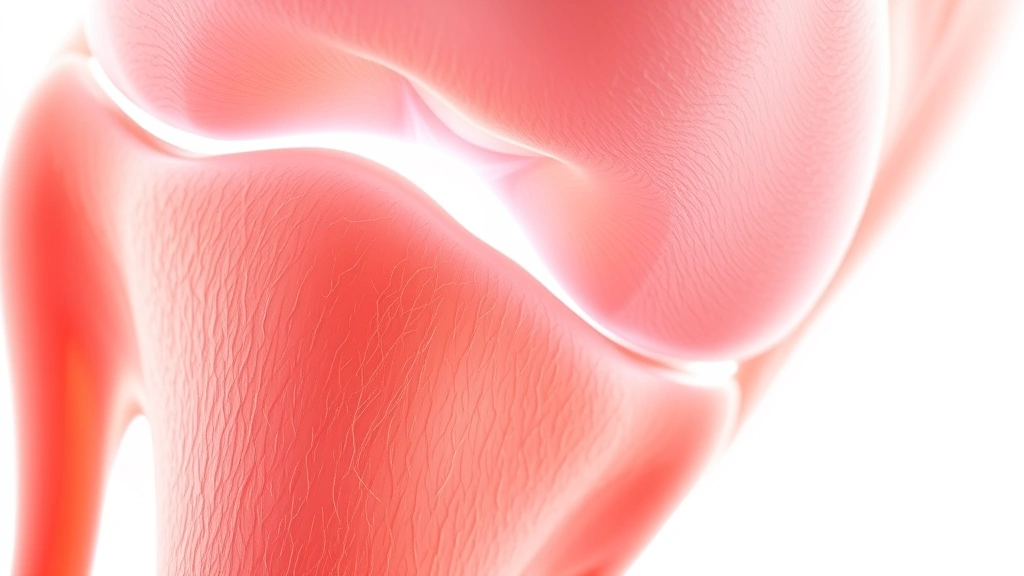

Wondering how long does it take to heal a meniscus injury? The answer isn’t one-size-fits-all, but most people see significant improvement within 2-6 weeks with proper care, while complete healing can take 2-3 months or longer depending on severity and treatment approach. Let me walk you through what actually happens during recovery and how to speed up the process.

Your meniscus is basically the shock absorber in your knee—two C-shaped pieces of cartilage that cushion the space between your femur and tibia. Think of it like the rubber padding in a workshop vice; when it wears down or tears, things don’t move smoothly anymore. A meniscus injury happens when you twist your knee awkwardly, usually during sports or a sudden directional change. The tear can be small and manageable or serious enough to require surgical intervention.

Here’s the real talk: how long does it take to heal a meniscus injury depends heavily on which type of tear you have. A minor tear in the outer region (the red zone where blood flow is good) might heal in 4-6 weeks with conservative treatment. A moderate tear could take 8-12 weeks. A severe tear requiring surgery? You’re looking at 3-6 months minimum, sometimes longer.

The meniscus has different zones based on blood supply. The outer edge gets excellent blood flow, so tears there heal faster. The inner portion has minimal blood supply, which means slower healing and sometimes permanent damage. Your doctor will determine which zone is affected and whether surgery is necessary.